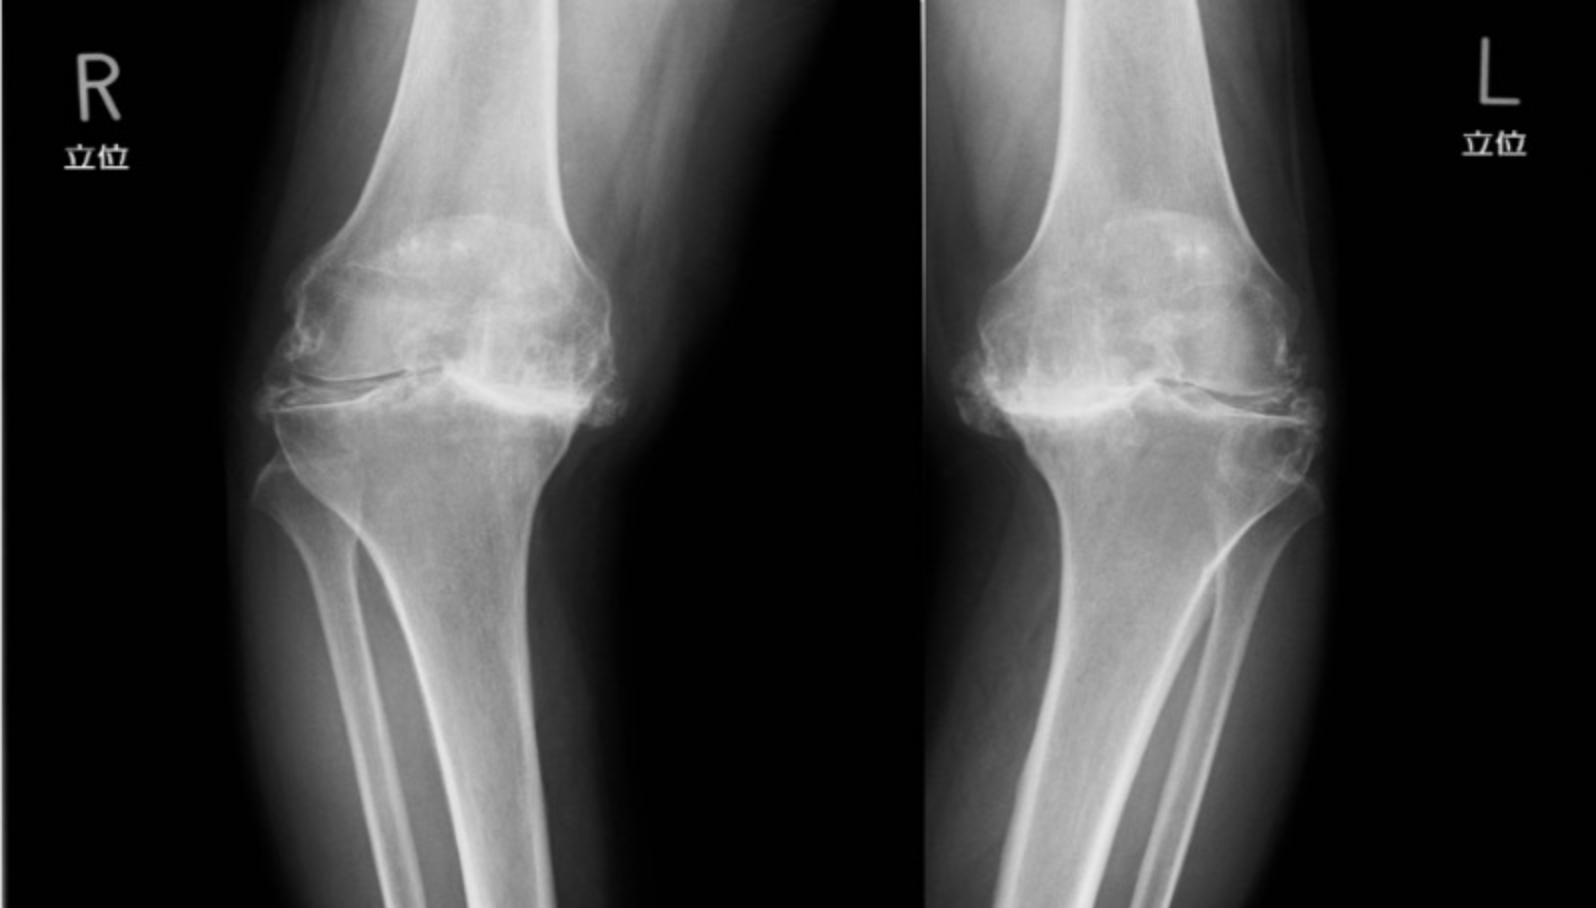

手術前後レントゲン画像

単顆型人工膝関節置換術

術前